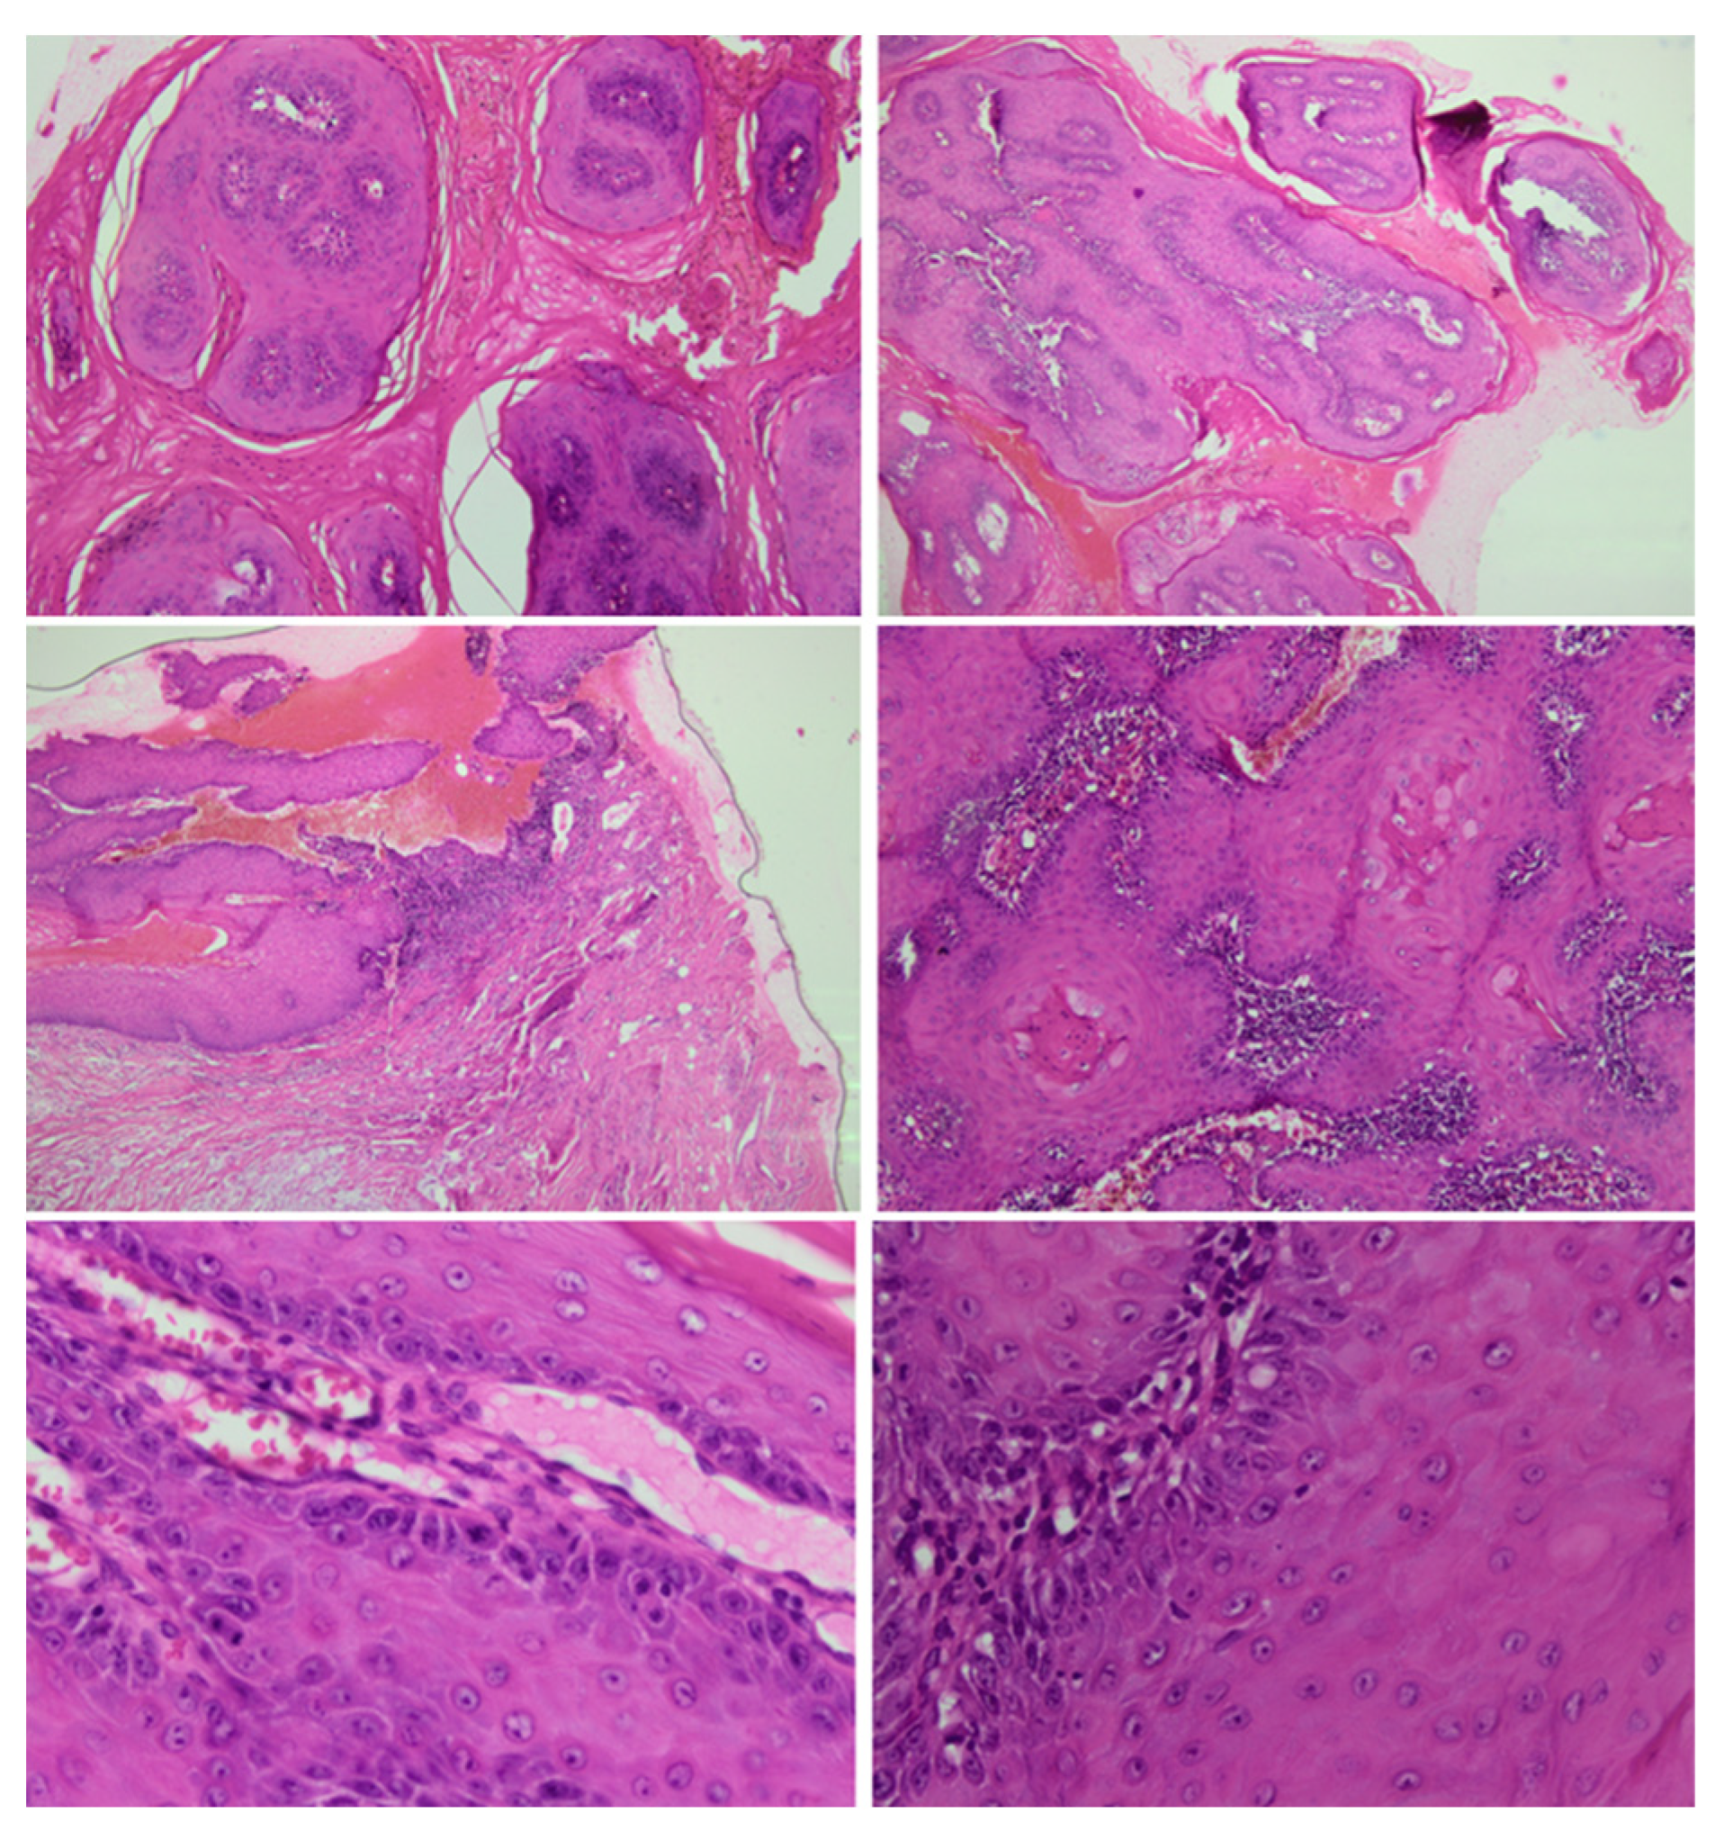

The anatomopathological examination showed papillary tumor proliferation covered by an acanthotic and keratinized stratified squamous epithelium. The interpapillary buds are enlarged and grow in depth. Minimal cellular atypia and lymphocyte infiltration were noted (Figure 3).

These findings support the diagnosis of an OVC.

Figure 3. Histologic features of the lesion: papillary tumor proliferation; acanthotic and keratinized stratified squamous epithelium; enlarged interpapillary buds growing in depth; minimal cellular atypia; lymphocyte infiltration.